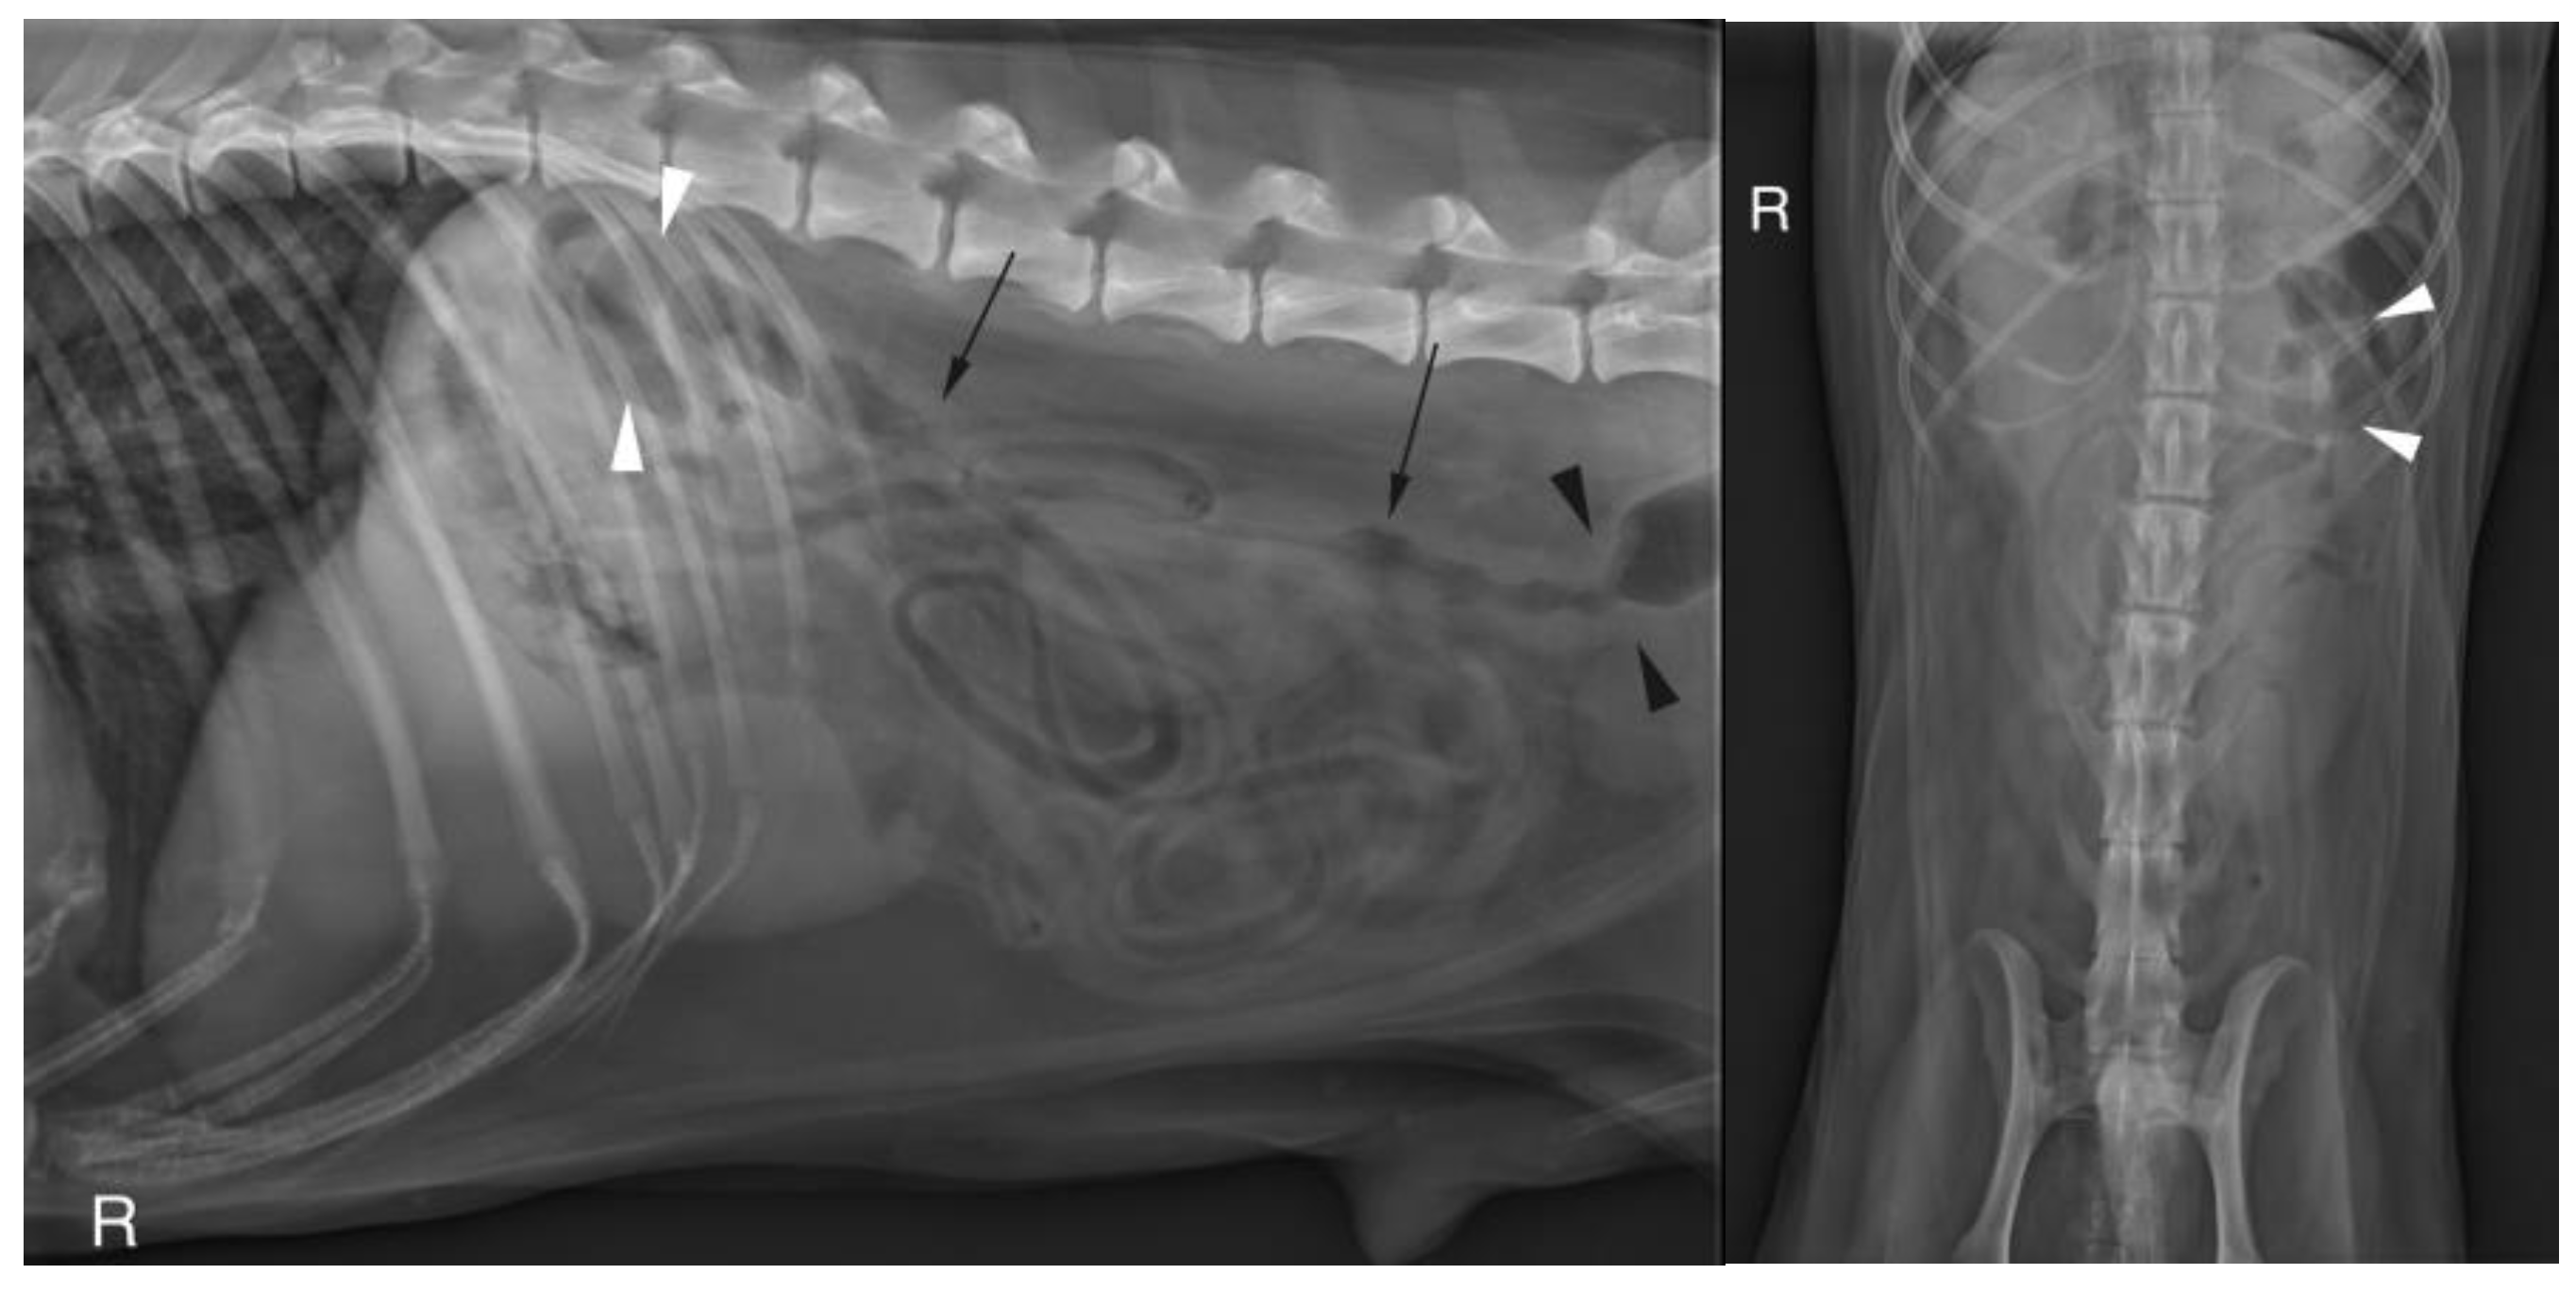

3.2.3. Abdominal Radiographs

Abdominal radiographs were acquired in 5 cases (4 cats and one dog). In two cats, the descending colon showed an abrupt ending with a total length approximately half as long as expected. No ascending nor transverse colon could be identified in these 2 cases (Figure 2). In the dog, the cecum appeared mispositioned in the left cranial abdominal quadrant and seemed associated with a focal area of colonic lumen narrowing 22 cm orally to the anus (Figure 3). Positive contrast colonography were performed in 3 cases (three cats) and allowed the diagnosis of partial colonic agenesis in all of them (Figure 4).

Figure 2. A. Right lateral radiograph and B. Ventro-dorsal radiograph of the abdomen of case 11, a 6 months old Scottish cat. The descending colon is shorter than expected and abruptly end in the mid left abdomen (white arrow heads). No other parts of the colon are identified.